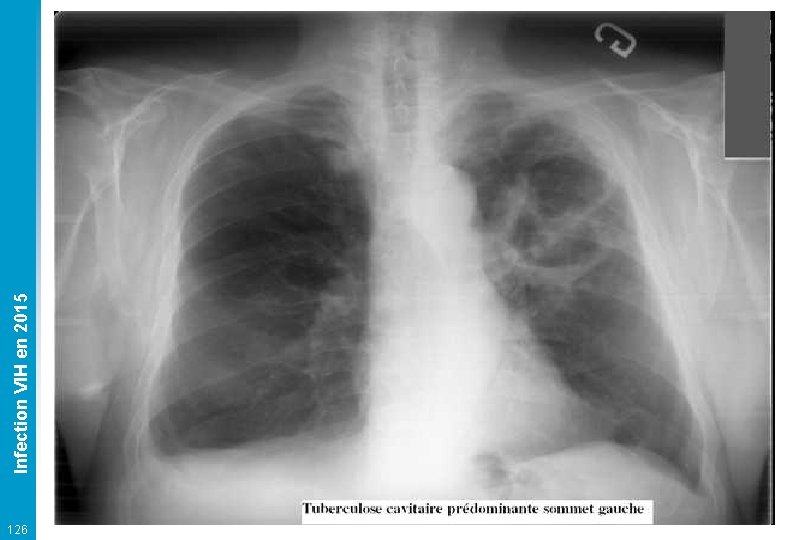

Tuberculose Infection VIH en 2015 q Mycobacterium tuberculosis (= bacille de Koch) le plus souvent endogène Localisations multiples (> 50 %) : pulmonaire et extra-pulmonaire Très fréquente (10 -15 %), régions d'endémie, précarité 125 • • Clinique : fébricule, AEG et autres selon la localisation Radio, crachats, tubages gastriques, LBA, LCR, moelle osseuse Examen direct par coloration Ziehl puis Culture (3 -6 sem. ) Autres localisations : ganglionnaire, hépatique, splénique, osseuse, cérébrale… q Traitement • 2 mois de rifampicine + isoniazide + pyrazimamide + éthambutol puis bithérapie rifampicine + isoniazide • Durée selon la localisation : 6 (pulmonaire isolée) à 12 mois (méningée) • Problème +++ interactions médicamenteuses avec les antirétroviraux Pas de prophylaxie secondaire

126 Infection VIH en 2015

Infection VIH en 2015 Tuberculose pulmonaire 127